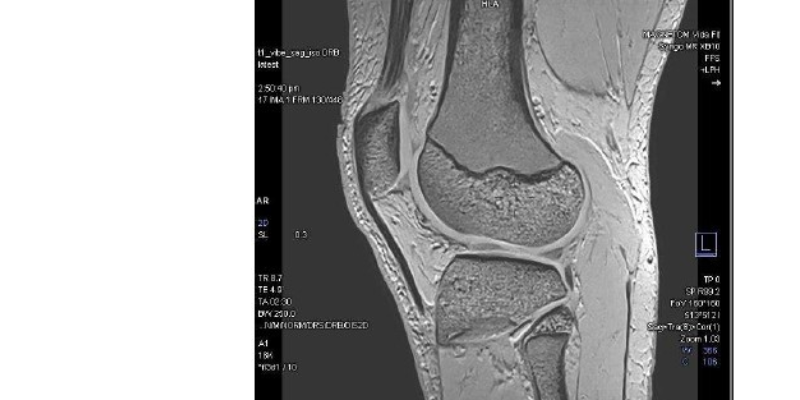

Canopy Imaging Brings Cutting-Edge, Sustainable MRI Technology to Ormiston

Canopy Imaging is proud to announce the installation of the MAGNETOM Vida Fit, a state-of-the-art 3T MRI system from Siemens Healthineers, at its Ormiston Canopy Imaging Clinic in Auckland. This achievement not only provides quicker, more precise scans for patients but also delivers on our commitment to sustainable healthcare.

The MAGNETOM Vida Fit also brings advanced AI-driven imaging and a patient-friendly design, offering exceptional diagnostic capabilities across neurology, oncology, musculoskeletal, and cardiovascular care. Features such as BioMatrix and Deep Resolve ensure consistent, high-quality results with reduced scan times, whilst the latest coil technology enhances patient comfort.